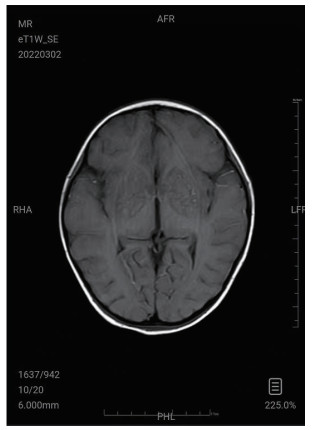

| 图 1 2月18日头部CT |

图 1为颅内弥漫脑实质肿胀,脑沟脑回显示不清,脑室受压,部分脑沟内可见高密度影,右侧小脑幕密度增高。中线结构居中。副鼻窦内见软组织密度影。图 2为大脑皮层、小脑及脑干形态肿胀,呈稍长T2信号影,有类似束带征。图 3为后颅窝去骨辨减压+小脑部分切除术后复查: 脑疝征象明显好转。